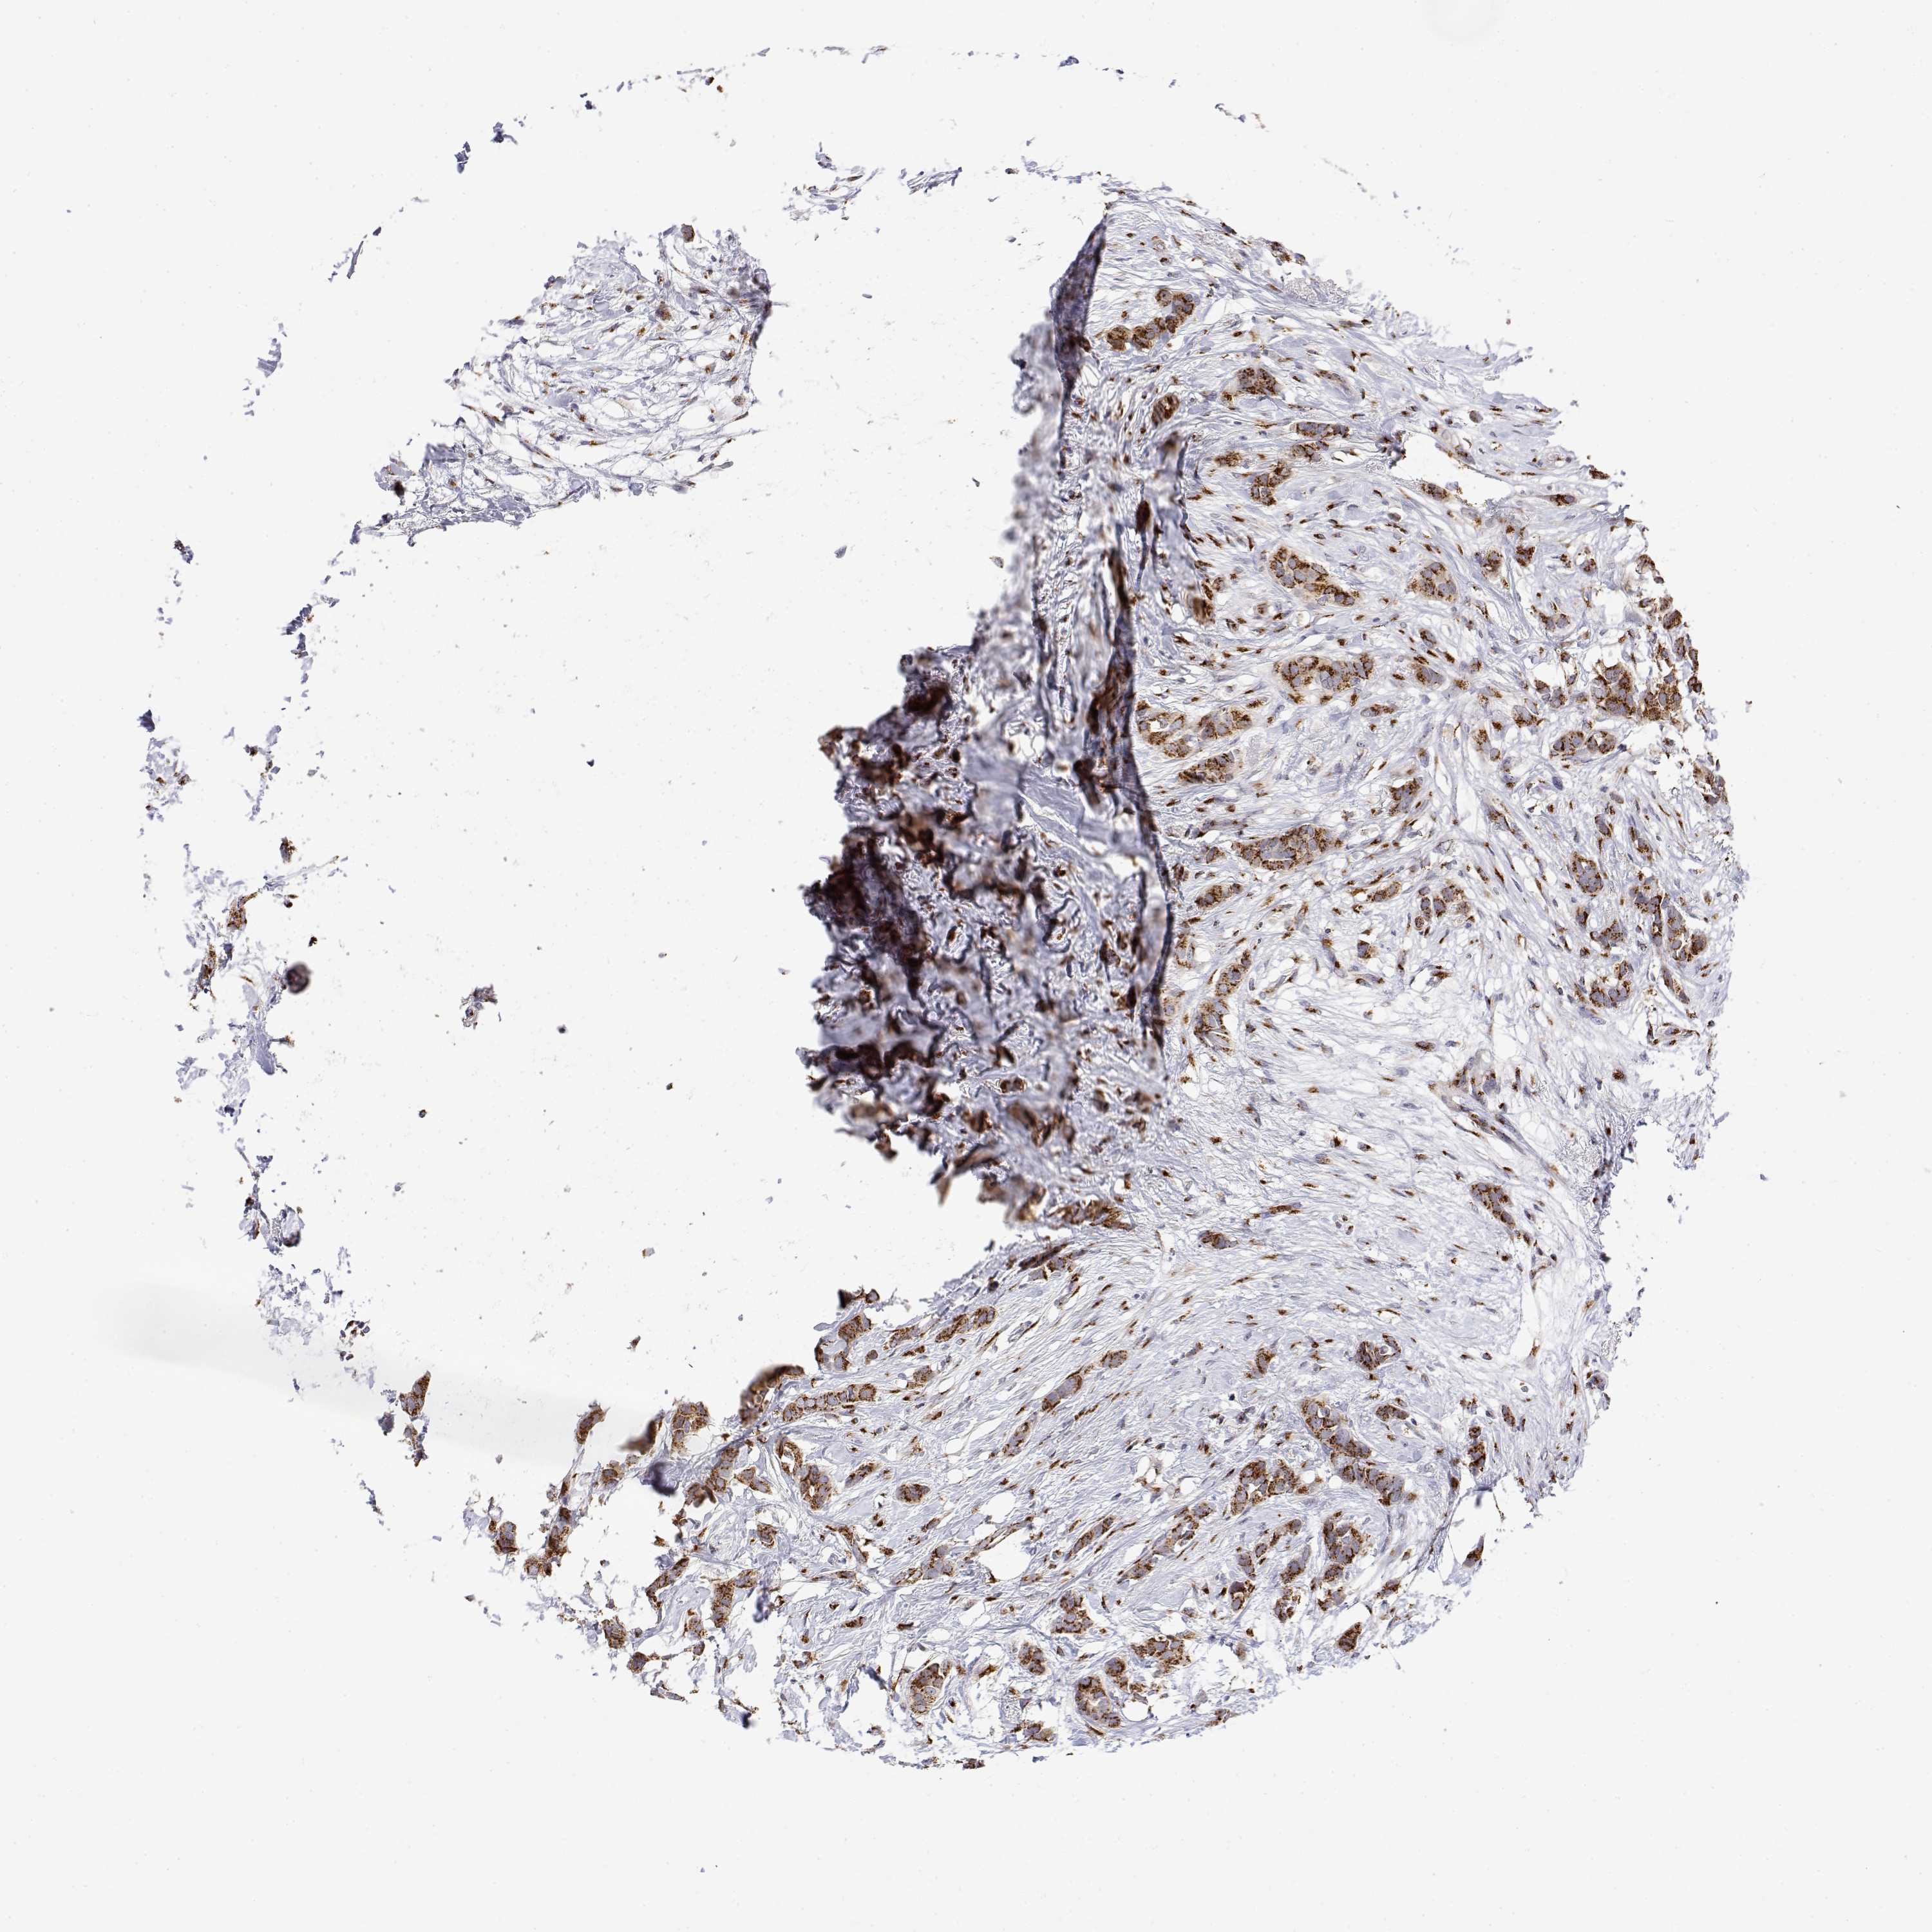

BRCA TCGA BRCA VALIDATION PROTEIN EXPRESSION